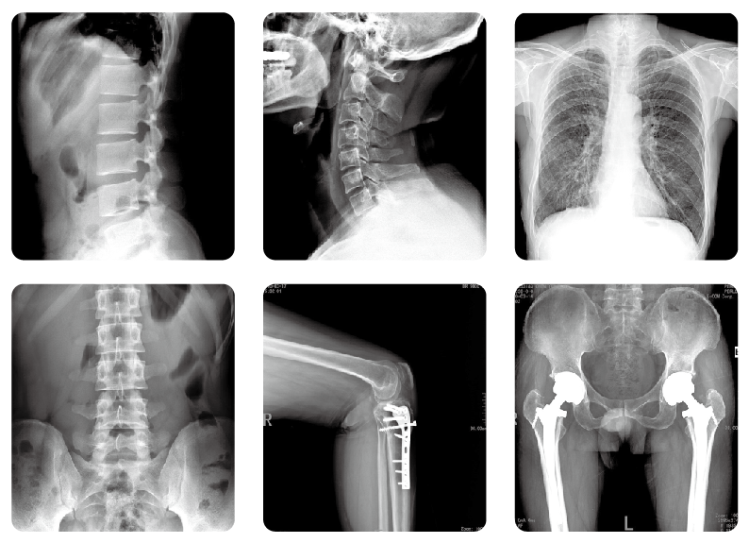

什么是镰刀臂dr?镰刀臂dr是一款拥有U型镰刀臂的dr设备,简称dr,主要用于对人体胸腔、四肢、盆腔、腰椎等部位进行摄片检查。它不同于传统的胶片成像技术,使医用诊断X线机实现无胶片化,并可将数字图像传送至其他设备或网络系统中去,开创了放射诊断新领域。

镰刀臂dr的特点是穿过人体的X射线直接投射到平板式图像探测器(简称DR板),然后应用计算机技术将数字图像采集、处理、运输及显示至监视器上,供医务人员观察人体脏器组织的图像,达到诊断的目的。